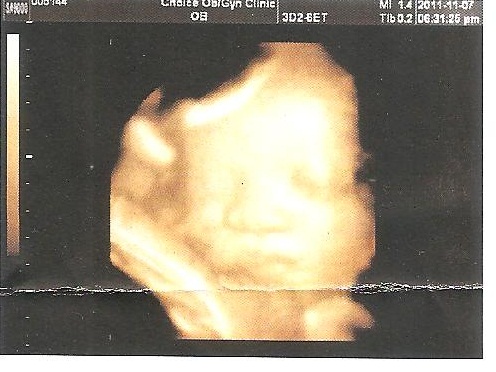

各位叔叔阿姨,大家好,這是爸比媽咪昨天帶我去照的超音波醫生阿姨說,37W6D的我,頭圍已經超過40周的標準了! 跟葛格一樣是個名符其實的大頭寶寶喔

體重也有3200g了,隨時都可以準備出來啦!外婆好喜歡我的澎澎臉,還說我這張照片跟貝貝葛格小時候很像耶!大家都很期待我的到來喲!